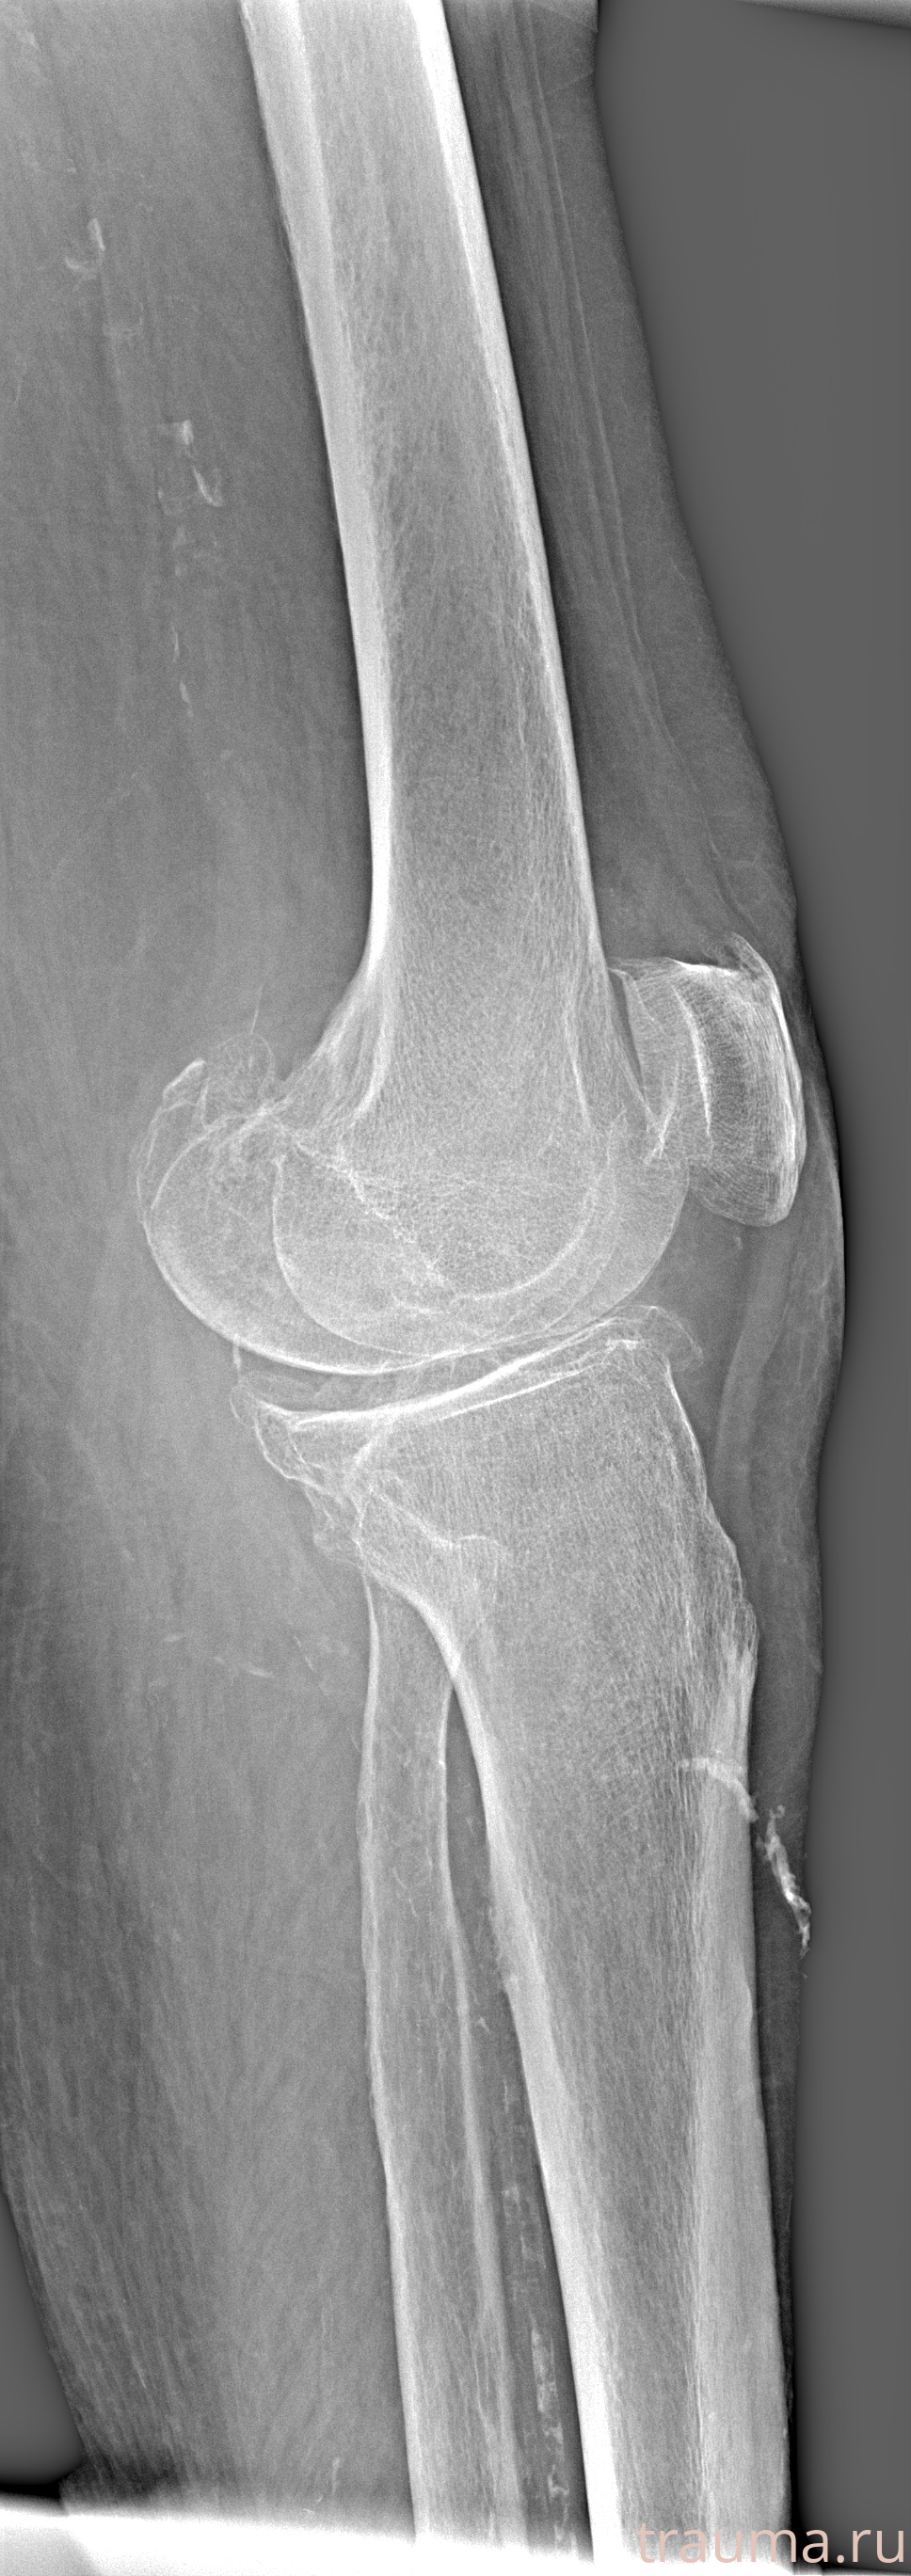

Рентгенограммы

Рентген на дому: по вашему адресу приезжает врач-рентгенолог, травматолог-ортопед с мобильным рентгеновским аппаратом, проводит диагностику травмы или заболевания, делает необходимые рентгенограммы, дает рекомендации по дальнейшему лечению. Получить качественные снимки в домашних условиях возможно благодаря уникальной методике, разработанной МосРентген Центром для института  Склифосовского

Яркость: 1   Контраст: 1   Инвертировать: 0 Увеличение: 1

Перетаскивайте мышь вверх/вниз для контраста, влево/право для яркости. Прокрутка колесом изменяет масштаб. Нажмите Сбросить для возврата к исходному изображению. При увеличении держите мышь в той области, которую хотите рассмотреть.